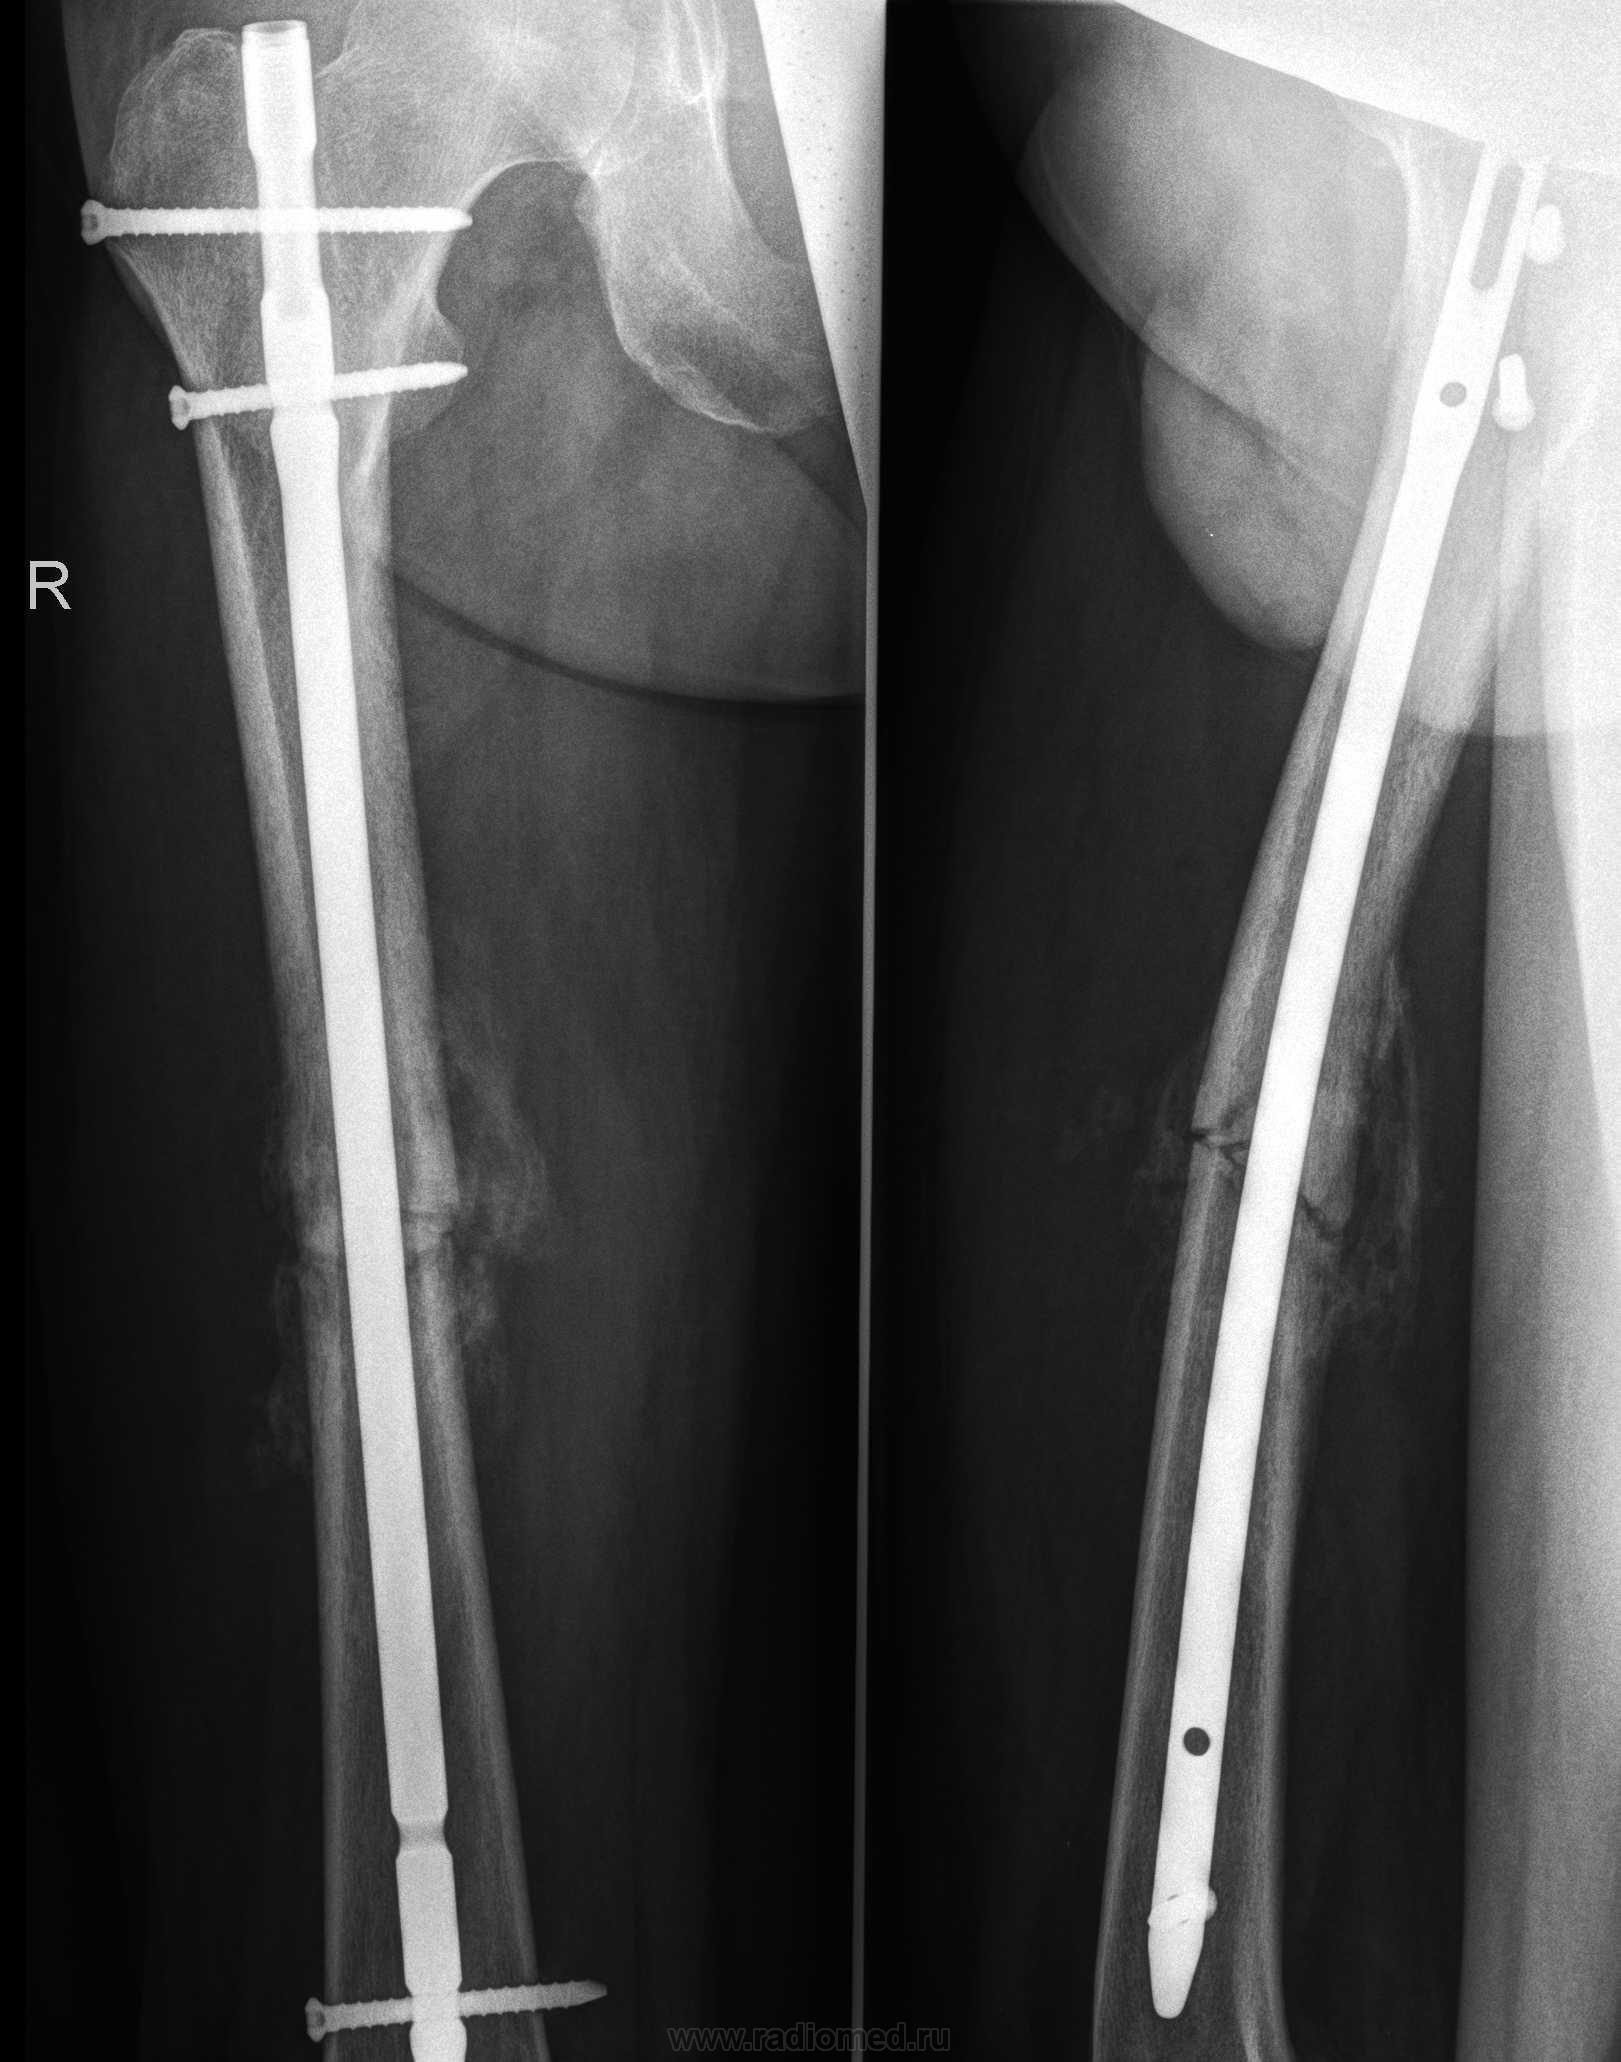

Классификация переломов диафиза бедренной кости: Иллюстрации и информация